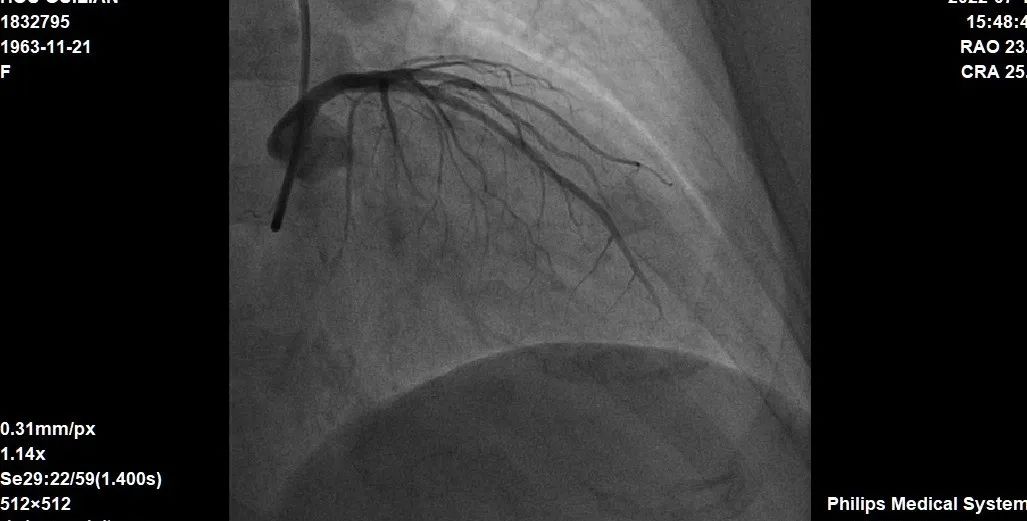

据西安市交通大学第一附属医院心内科主任郭宁介绍,患者是一位58岁的女性冠心病患者,诊断:冠状动脉粥样硬化心脏病,不稳定型心绞痛、心功能II级。入院后完善相关检查后,于2022年7月12日进行手术,造影显示冠状动脉左前降支近中段有严重狭窄伴重度钙化。经团队充分讨论后,术中IVUS检查提示270度环形钙化,在血管内超声评估和指导下,随后采用Shockwave冲击波能量钙化斑块碎裂技术,经过多个周期的冲击波治疗,精确碎裂冠状动脉内膜和中膜下钙化病灶后,最后顺利置入支架。